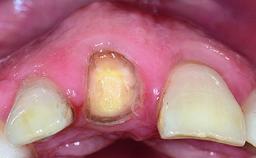

A 30-year-old patient presented at our clinic with a chief complaint of pain in her endodontically treated right maxillary central incisor (tooth 11) with a post-and-core and a fixed single crown. She had a very high lip line, a medium to thin soft-tissue phenotype, and a medium scalloped gingival contour. She also had high esthetic expectations because of her young age and beautiful smile. However, her expectations were realistic and she understood the risks of the treatment. At the initial clinical examination there was a slight mobility of tooth 11; no fistula was observed. The patient also had a single crown on the adjacent tooth 21. Both restorations were old and esthetically deficient. A digital periapical radiograph showed a very small periapical radiolucency, a thick intraradicular post, and no separation between root fragments.

Abutment Type Customized

Prosthesis Type FDP